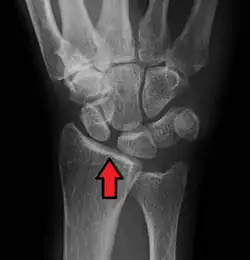

X-ray images indicate scapholunate ligament instability when the scapholunate distance is more than 3 mm, which is called scapholunate dissociation.[7] A static scapholunate instability is generally readily visible, but a dynamic scapholunate instability can only be seen radiographically in certain wrist positions or under certain loading conditions, such as when clenching the wrist, or loading the wrist in ulnar deviation.[6]

Scapholunate ligament disruption associated with a Colles' fracture